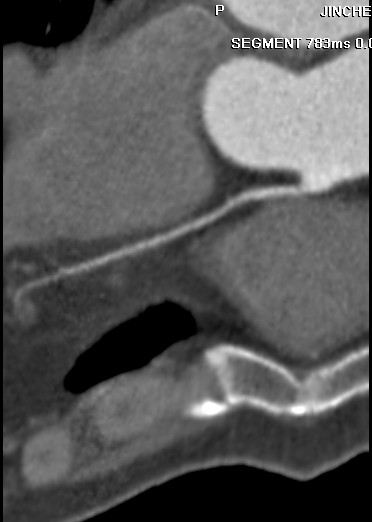

标题: CT24400:患者54岁,心前区不适进行心脏冠脉造影检查。 [打印本页]

标题: CT24400:患者54岁,心前区不适进行心脏冠脉造影检查。

患者54岁,心前区不适进行心脏冠脉造影检查。高手看看有问题没有?